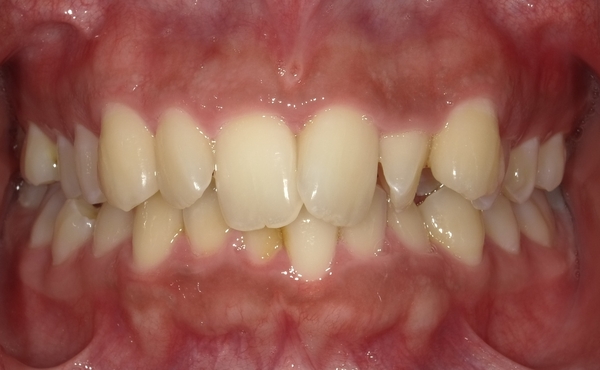

ガタガタとした歯並びや八重歯(叢生)CASE53